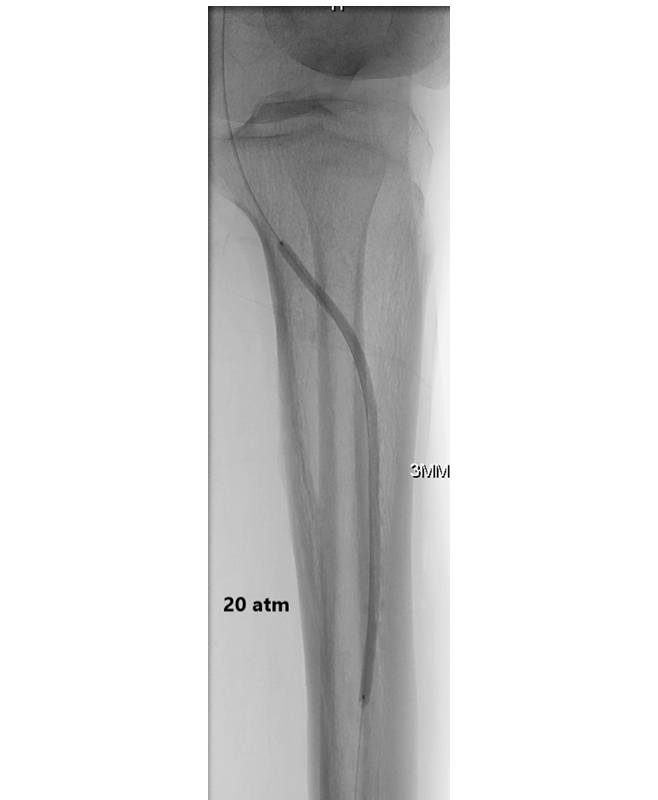

钙化斑块的病理类型分为内膜性钙化(常见于动脉粥样硬化晚期,呈片状或结节状)、中膜性钙化(Mönckeberg硬化,多见于糖尿病和慢性肾病,呈环形、连续状)以及混合型。其中,中膜环形钙化对球囊扩张的抵抗最强,因为其钙化层位于平滑肌层外,球囊压力无法有效撕裂该结构。常规高压球囊(额定爆破压20-24 atm)在遇到360°中膜钙化时,常常出现“狗骨征”(dog-boning)或局部夹层,而管腔获得极小。斑块旋切设备(如TurboHawk、JetStream)对浅表内膜钙化有效,但对深层或环形中膜钙化效果有限,且有远端栓塞和穿孔风险。血管内碎石(Intravascular Lithotripsy, IVL)通过冲击波选择性作用于钙化,对中膜钙化有效,但设备昂贵、球囊尺寸限制(目前最小IVL球囊直径为2.5mm,如Shockwave M5+,适用于2.5-4.0mm血管,仍无法用于更细的踝下动脉如足背动脉直径1.5-2.5mm)。

压裂治疗前后及球囊血管成形术后病变形态与IVUS评估的MLA代表性病例。A 初始血管造影显示右侧股总动脉存在重度钙化斑块。B 初始IVUS评估示术前最小管腔面积(MLA)为2.1 mm²(管腔直径:1.7 × 1.3 mm)。C、D 使用7.0 mm非顺应性球囊行球囊血管成形术后,后续血管造影及IVUS显示残余狭窄33%,术中MLA为5.8 mm²(管腔直径:3.0 × 1.7 mm)。E 压裂治疗后,最终血管造影显示满意影像,狭窄率17%。F 压裂后IVUS评估显示术后MLA为20.5 mm²(管腔直径:6.1 × 4.3 mm)。缩略语:IVUS,血管内超声;LD,管腔直径;MLA,最小管腔面积。